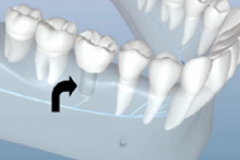

早期矯正

技(jì )術優勢

兒童優選 · 專為(wèi)3~12歲兒童設計

量身定制 · 針對孩子不同情況定制矯正計劃

正牙助萌 · 同步完成獲得理(lǐ)想面型